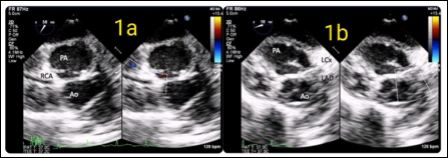

Preoperative trans-thoracic echo revealed d-TGA with large subpulmonic VSD and small OS-ASD. Additional basal muscular VSD was seen. Child was taken up for ASO. After induction of anaesthesia as per institutional protocols, Transesophageal Echocardiography (TEE) was done using a Philips S8-3t transesophageal probe and iE33 workstation. On mid-esophageal aortic valve short axis view at an omniplane angle of 60°, pulmonary artery was posterior and to the right. Aorta was anterior and left. The right coronary artery was coursing from the right coronary sinus towards the right ventricle without any branching (Figure1). Left coronary artery was coursing to itsbifurcation at an omniplane angle of around 20°, indicating the two coronaries were not in the same plane (Figure 2).

Figure 1: Transesophageal mid-esophageal short axis view showing right and posteriorly places Pulmonary Arteries (PA), left and anteriorly placed Aorta (Ao) and the Right Coronary Artery (RCA) originating from the right facing sinus.

Figure 2: Transesophageal modified mid-esophageal short axis view showing the left coronary artery originating from the left facing sinus and dividing into to left Anterior Descending (LAD) and left Circumflex (LCx) arteries.